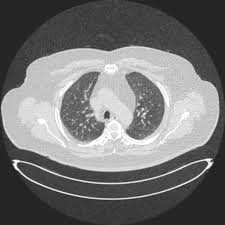

4) 정기검진

특히 흡연력 있는 40세 이상 성인은 저선량 CT 검진을 권장합니다.